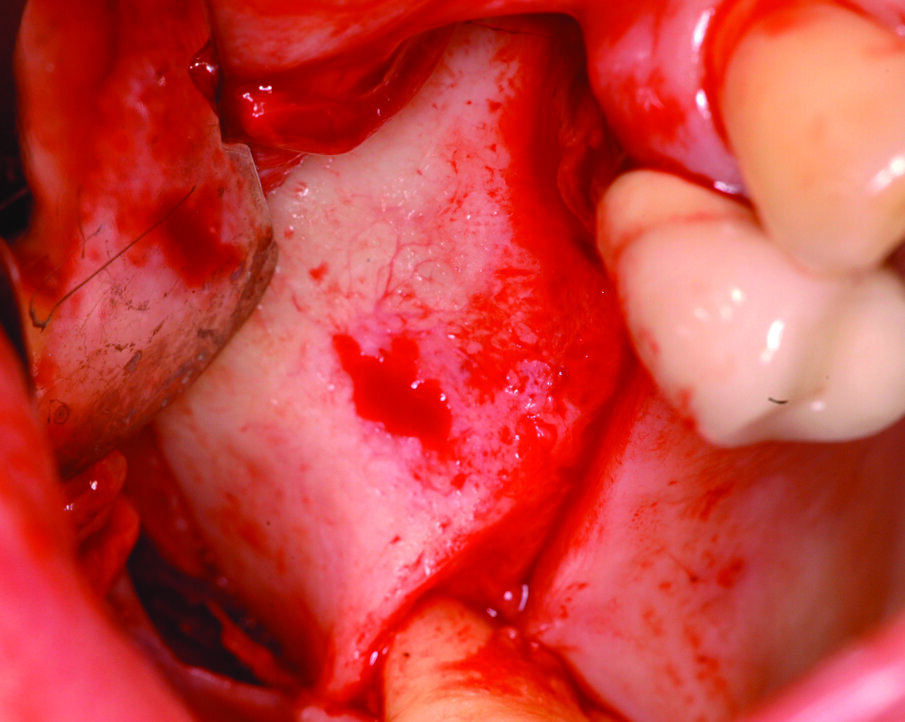

Di seguito viene valutata l’anatomia del seno mascellare, in particolare analizzando l’angolo tra la parete mediale e la parete laterale del seno, che ne determina l’ampiezza3. Vista l’assenza di setti e data la buona ampiezza del seno mascellare viene scelto un approccio per via laterale, in grado anche di consentire un miglior controllo dei volumi ossei innestati, considerando che gli impianti da inserire sono due. Si procede, quindi, con l’allestimento di un lembo a tutto spessore con tagli di scarico sia mesiale che distale (Figg. 2, 3) e a un’antrostomia per riflessione con bisturi piezoelettrico (Surgybone, Silfradent, Italia) (Fig. 4), che permette un miglior controllo dell’osteotomia4-5, riducendo il rischio di perforazione della membrana di Schneider.

Una volta eseguito il disegno dell’antrostomia (Fig. 5), si procede al sollevamento della membrana con tecnica manuale (Figg. 6, 7) e all’iniziale inserimento di biomateriale granulare 0,5-1 mm (AlphaBio’s Graft, Alpha-Bio Tec, Israele). La corticale viene lasciata integra e aderente alla mucosa schneideriana in modo da diventare il futuro pavimento dell’antro (Fig. 8), anche per supportare il collasso della membrana durante il periodo di guarigione. A protezione della stessa è inserita una spugnetta di collagene equino (Condress, Smith&Nephew, UK). Contestualmente si procede con l’inserimento di due impianti autofilettanti SPI 3.75 x 13 mm (Alpha-Bio Tec, Israele) (Figg. 9, 10) e, al termine, viene ultimato il riempimento con biomateriale (Fig. 11). L’antrostomia viene poi coperta con una membrana riassorbibile 15 x 20 (AlphaBio’s Graft, Alpha-Bio Tec, Israele) e il lembo viene passivato e suturato con due linee di sutura 5-0: una a materassaio orizzontale e l’altra con punti staccati (Vicryl, Ethicon, USA) (Fig. 12). La paziente viene dimessa con la seguente terapia farmacologica: amoxicillina cpr 1 gr (1 cpr ogni 12h per 6 giorni), Prednisone cpr 25 mg (2 cpr per due giorni a scalare) per il controllo dell’edema post-operatorio e sciacqui con clorexidina 0.2% dal giorno successivo (1 sciacquo al giorno per 15 gg). Le suture sono rimosse a 15 giorni e la paziente è inserita in un programma di recall a cinque settimane per gestire eventuali complicanze durante la maturazione dell’innesto. Viene eseguito il secondo tempo chirurgico dopo 6 mesi e, verificata l’avvenuta osteointegrazione degli impianti, vengono rilevate le impronte e il caso è finalizzato con due corone unite in metallo ceramica (Figg. 13-15). Al termine della riabilitazione, visto il buon mantenimento igienico, la paziente viene inserita in un programma di follow-up a sei mesi (Figg. 16, 17).

Fig. 8_Particolare dell’antrostomia per riflessione, in cui è possibile notare l’integrità della membrana.